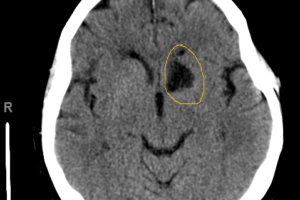

Infarct of the left recurrent artery of Heubner

Recurrent artery of Heubner

The recurrent artery of Heubner is a branch off the proximal A2 or distal A1 segment of the anterior cerebral artery (ACA) and supplies the head of the caudate nucleus, as well... Read more »